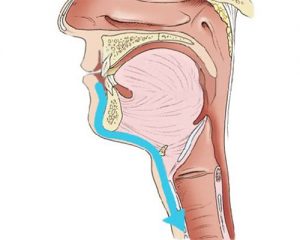

Endoskopowe operacje tarczycy metodą TOETVA

Technika endoskopowego wycięcia tarczycy TOETVA jest procedurą małoinwazyjną w której dostęp operacyjny do tarczycy następuje przez przedsionek jamy ustnej, a nie jak w klasycznej chirurgii tarczycy poprzez wykonanie cięcia w dolnej części szyi. Zabieg rozpoczyna założenie trzech trokarów: jednego o średnicy 10mm oraz dwóch o średnicy 5mm przez które następnie wprowadzane są narzędzia chirurgiczne. Wykonanie procedury metodą endoskopową z zastosowaniem neuromonitoringu śródoperacyjnego sprawia, że zabieg jest optymalnie bezpieczny dla pacjenta, pozwala mu na uniknięcie cięcia na skórze szyi i uzyskanie dobrego efektu kosmetycznego jak również pozwala na skuteczne skrócenie czasu rekonwalescencji. W ramach przygotowania do zabiegu metodą TOETVA rekomendowana jest wcześniejsza konsultacja stomatologiczna, która ma na celu wykluczenie ewentualnych ognisk zakażenia w jamie ustnej. Zabiegi metodą TOETVA w Szpitalu na Klinach realizuje prof. Marcin Barczyński wraz z zespołem.